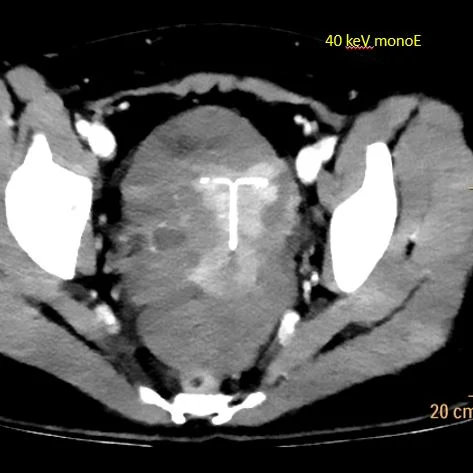

40 keV monoenergy image shows small right adnexal cyst.